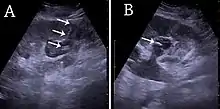

Under interventional radiology, the subject either lies down on the side or in a prone position. An area is selected below the 12th rib, bounded laterally by the posterior axillary line and the muscles of the spine and from below by the pelvic bone. The exact area is then located by ultrasound. Local anesthetic infiltration is used to numb the area. Then a needle would pass through to make the puncture on the kidney. Then, urine from the kidney is aspirated and check for its contents. If the urine is clear, dye will be injected to delineate the renal pelvis and renal calyx. If the urine is turbid, it means the urine is infected. Dye injection is avoided in case of turbid urine to prevent the spread of infection to other parts of the urinary system.[4] Then, a guidewire is inserted into the through the needle and parked within the upper renal calyx or within the ureter under fluoroscopy guidance. Then the puncture tract is dilated using a dilator.[4] Various types of catheters such as pigtail catheter[5] or Malecot catheter (a catheter that has a special mechanism for preventing blockage in case of thick pus in pyonephrosis and not easily dislodged when compared to pigtail catheter) can be used.[4] The catheter is inserted through the guidewire and is secured in place by suturing it to the skin. The other end of the catheter is attached to a urine bag for drainage of urine from the kidney.[4]